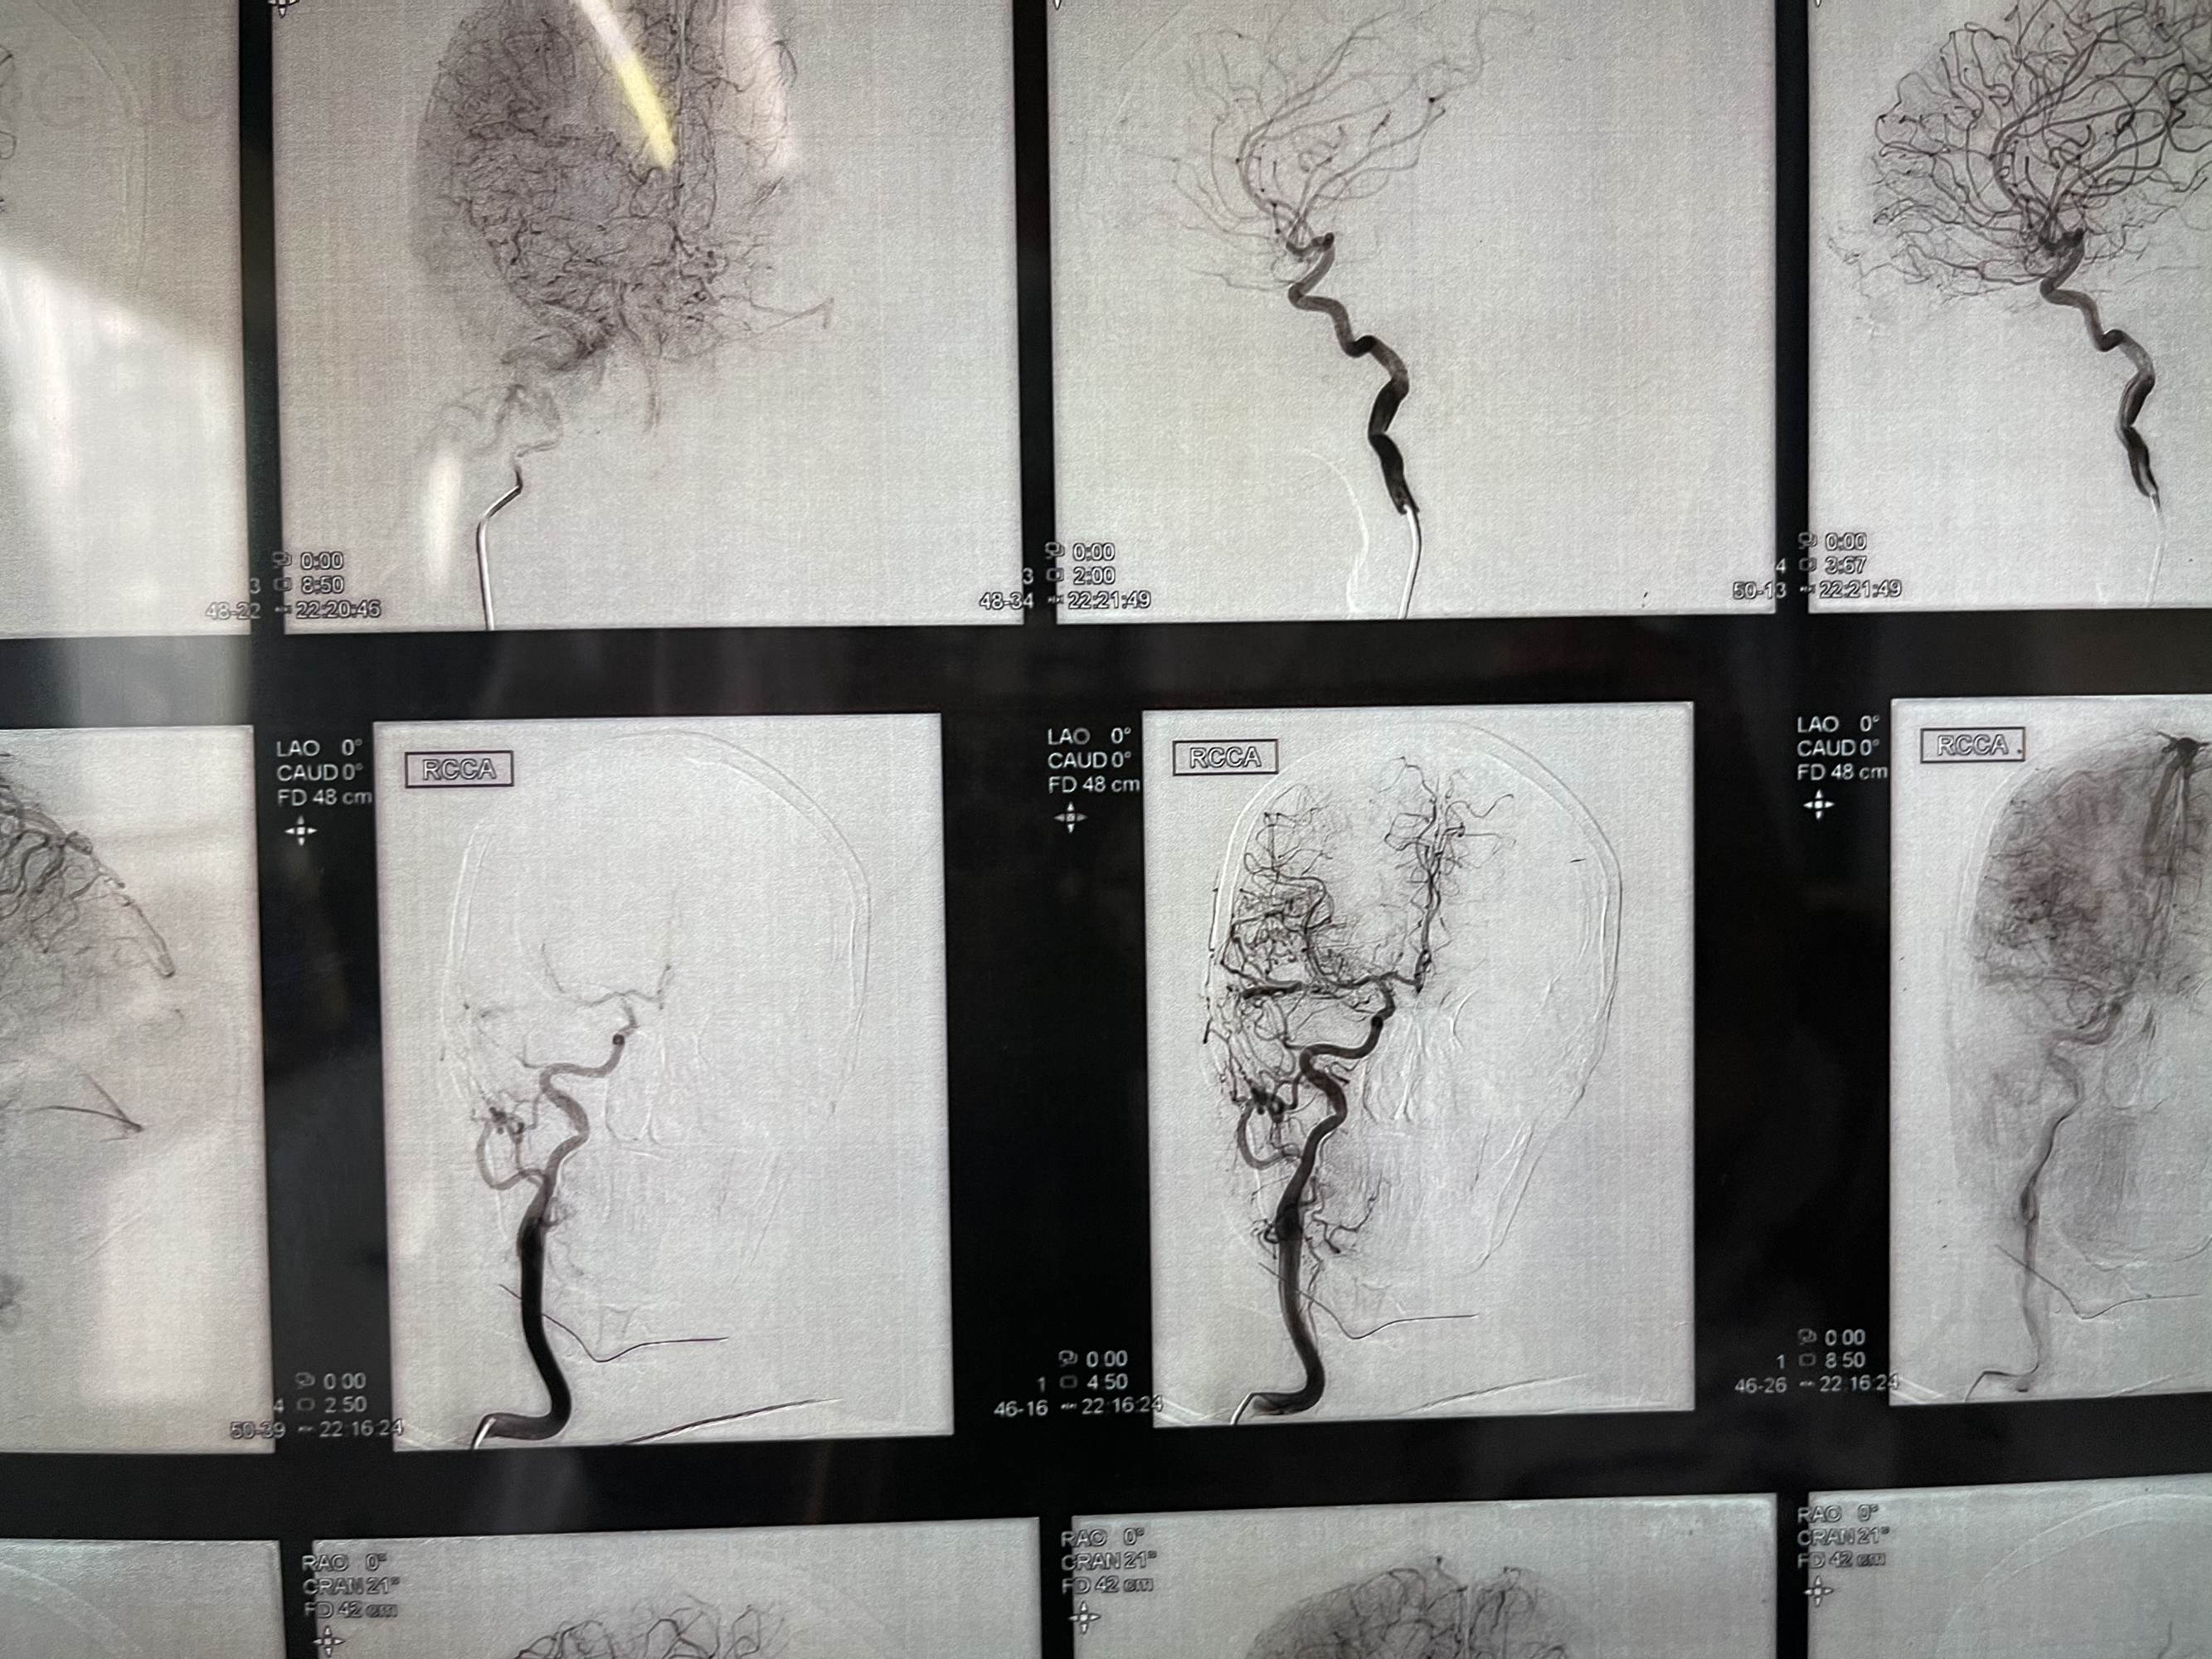

微导管到达瘘口,打胶

术后,清爽了,瘘口都不在显影,

不减影,看看胶

微导管到达瘘口,打胶

术后,清爽了,瘘口都不在显影,

不减影,看看胶